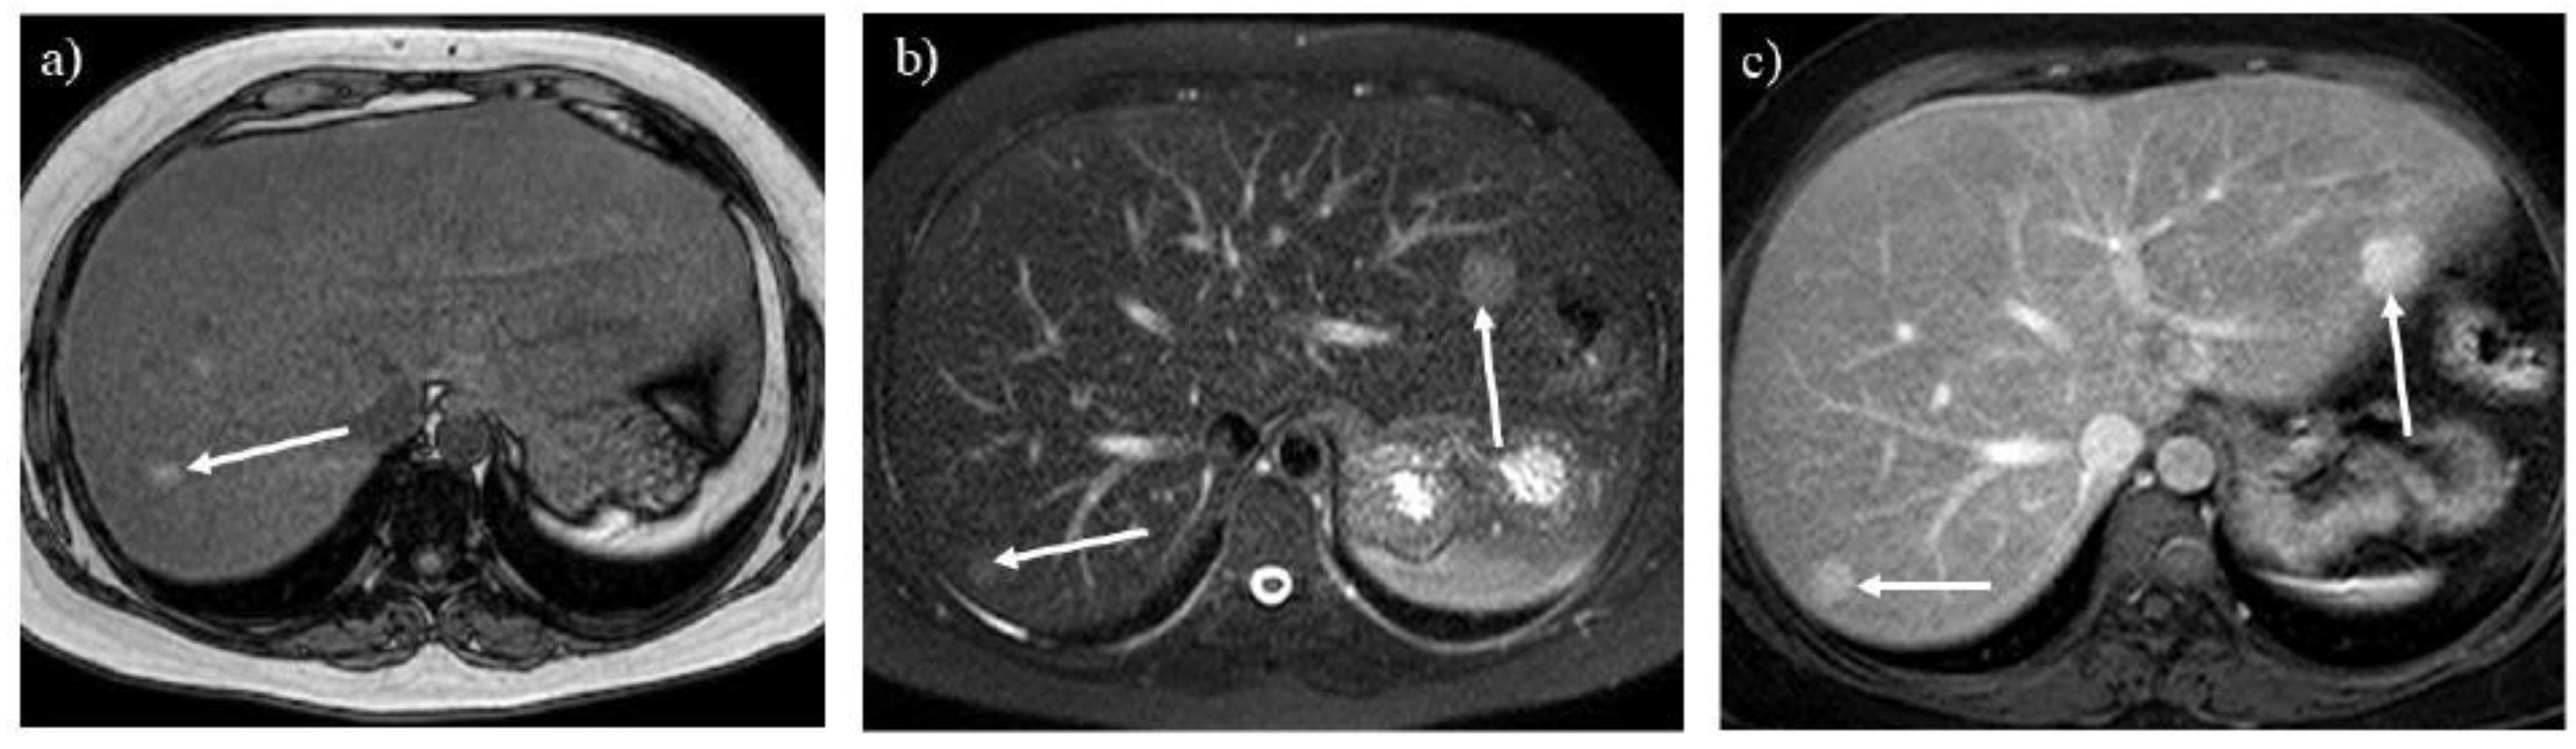

Hepatic steatosis is often associated with GSDs because of malnutrition and lipid metabolism disorders [3,6]. Dual-echo T1-weighted imaging reveals hepatic steatosis (Figures 6A and 7A) [9]. It is also useful for monitoring the severity of hepatic steatosis. The liver signal normalizes on opposed-phase T1-weighted imaging in patients with GSD type I following successful dietary therapies (Figure 6B).

Hepatic adenoma and adenomatosis are common complications of GSDs [1,2,3,6,7,8]. Some genetic alternation may contribute to a larger hepatic adenoma in patients with GSD type Ia [3]. Different from hepatic adenomas without GSDs, those associated with GSDs are often found in male patients and multiple lesions (i.e., hepatic adenomatosis) and increase in size (Figures 3B, C, 7B and C) [17,18]. The hepatic adenoma associated with GSDs are not related to contraceptives. It is clinically problematic to differentiate between a growing hepatic adenoma and hepatocellular carcinoma. Indeed, hepatic adenoma can transform into hepatocellular carcinoma in the older patients with GSDs, exhibiting similar imaging appearances in GSDs (Figures 3C, 7B and 8) [9,17]. Multimodality imaging surveillance should be performed once a hepatic tumor presenting strong enhancement in the arterial phase is identified in patients with GSDs [6,9].

Figure 7. Opposed-phase T1-weighted imaging (A) demonstrates hepatic steatosis and hepatic adenoma in a 31-year-old woman with glycogen storage disease type Ia (arrow). T2-weighted (B) and contrast-enhanced T1-weighted (C) imaging show hepatic adenomatosis (arrows).

Figure 8. A liver tumor shows high intensity on T2-weighted imaging (A) in a 55-year-old woman with glycogen storage disease type Ia (arrow). The tumor grew rapidly over 1 year (B, arrow). The tumor shows marked hyperintensity on diffusion-weighted imaging (C, arrow), which is pathologically proven to be a hepatocellular carcinoma.